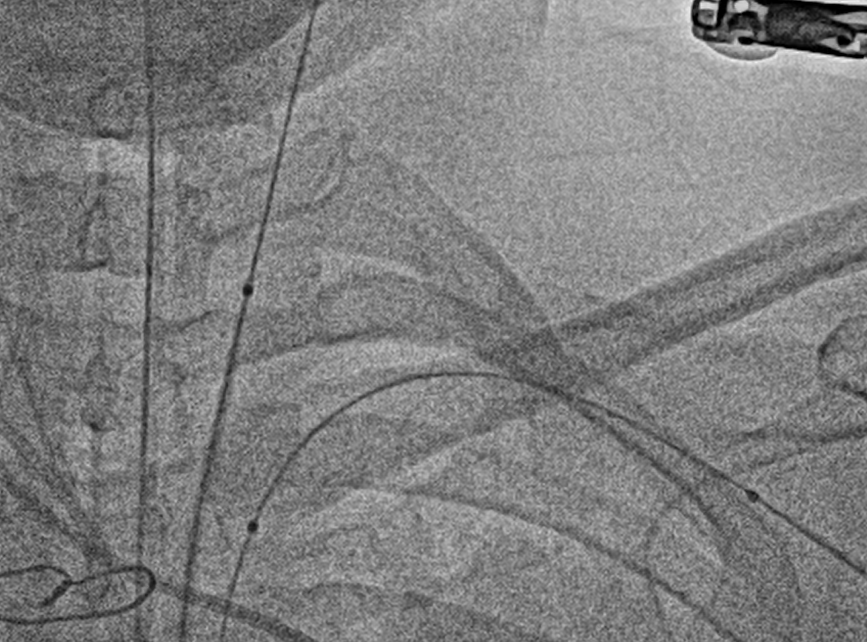

Cerebral Protection was done with one filter and two peripheral balloons

Transeptal Puncture was done and was later exchanged with 8.5fr deflectable Agilis sheath

Bilateral Radial and Femoral artery access taken along with Right Femoral vein under Ultrasound guidanceCarotid filter was placed in Right carotid artery through Right femoral arteryTwo Peripheral balloons were kept in left common carotid and left subclavian through left femoral and radial artery routeTranseptal puncture through right femoral vein was done and was later exchanged with 8.5fr deflectable Agilis sheathThrough Agilis sheath valve orifices was crossed with 0.032 Terumo wireUpper Orifice was dilated with 12x140mm peripheral balloonCentral Orifice was dilated with 5x60mm peripheral balloonLower Orifice was dilated with 10x140mm peripheral balloonPost Procedure Good movement of both leaflets , still upper leaflet movement was not satisfactory.6fr Decapolar mapping catheter was used for pecking the upper leaflet and later again it was dilated with 12x140mm peripheral balloon.Movement of both leaflets were good